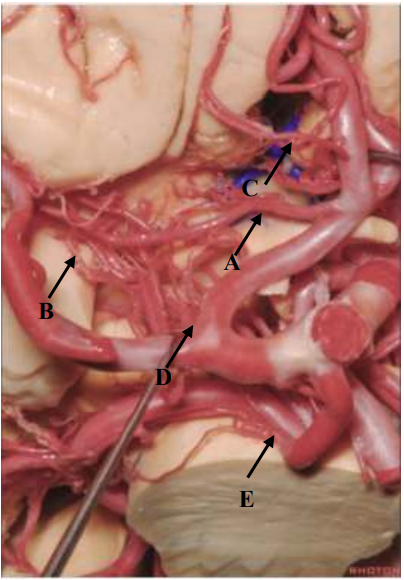

Qual seta aponta para a Artéria Recorrente de Heubner?

Provas